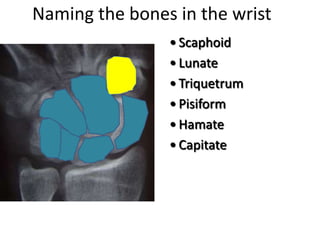

- Naming the bones, joints, tendons, nerves and skin landmarks of the hand and wrist.